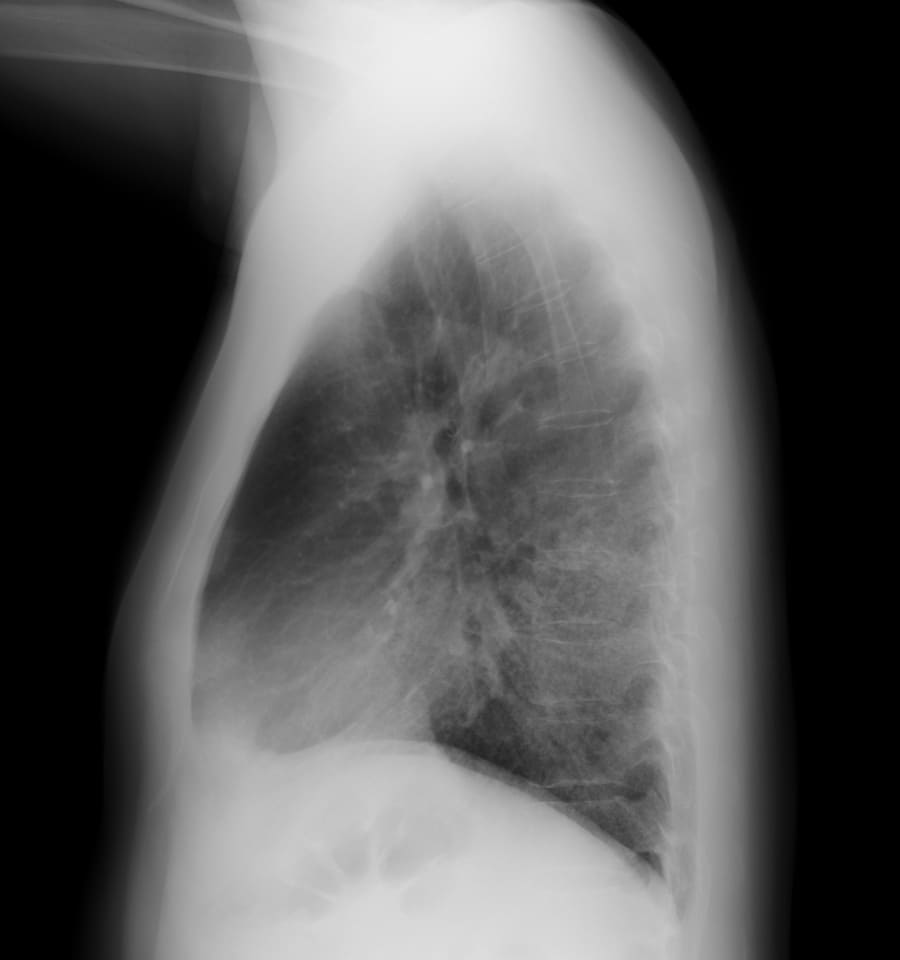

- Q3 呼吸困難を訴える40代男性(事務職)

呼吸困難を訴える40代男性(事務職)

DATA 1| X 線検査結果

画像にマウスオン(またはタップ)すると虫眼鏡で拡大できます